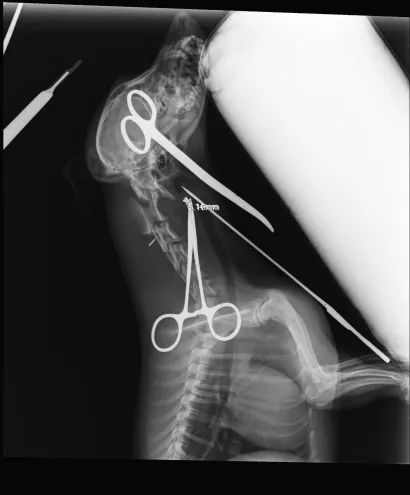

Maleni pas mješanac pogođen je dijabolom u vrat, a budući da je metak ostao smješten na nezgodnom mjestu blizu kralježnice, veterinar Mate Karaula iz Daruvara koji liječi Lenu, odustao je od vađenja metka zbog daljnjeg rizika po kujicu.

Prema nalazu veterinara dr. Mate Karaule, rendgenska snimka pokazala je da se metak, točnije dijabola, nalazi u području između atlasa i aksisa – dijela vratne kralježnice.

- Veličina projektila procijenjena je na 6,10 do 5,16 milimetara, a zbog dubine položaja i blizine kralježnice procijenjeno je da bi pokušaj vađenja mogao izazvati ozbiljne komplikacije. Zbog toga se odustalo od kirurškog vađenja metka.

Pas je primio injekcijsku sedaciju, obavljene su dvije rendgenske snimke i kirurška obrada rane, kazao nam je dr. Karaula.